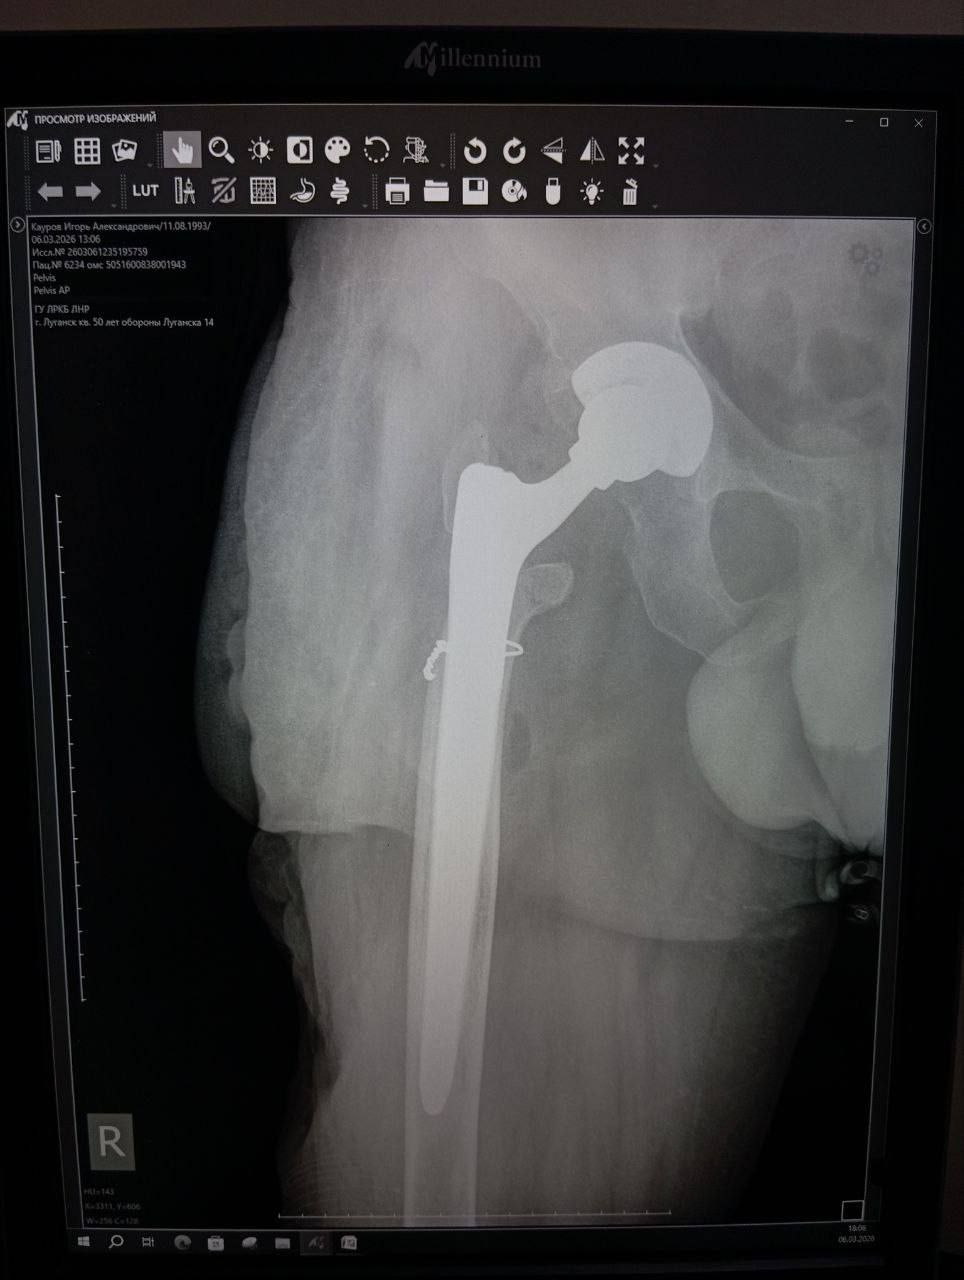

ЧУДО ПРОИЗОШЛО 5 МАРТА 2026 ГОДА В ЛУГАНСКЕ.

В Луганской республиканской клинической больнице бригада травматологов-ортопедов провела операцию, которая стала финальным аккордом этой долгой истории.

Вместо стандартной замены сустава пациенту выполнили сложнейшее вмешательство с использованием ревизионных систем эндопротезирования, в ЛНР такую операцию провели впервые. Главная задача хирургов заключалась не просто в установке импланта, а в восстановлении биологической оси конечности и компенсации укорочения.

Хирургам пришлось работать в рубцово-измененных тканях после десятка предыдущих операций, убрать очаги инфекции (некроэктомия) и с помощью специальных ревизионных компонентов буквально «собрать» сустав заново, вернув ноге физиологическую длину. Для пациента это означает шанс не просто избавиться от боли, но и забыть о хромоте, вернуться к нормальной походке.

05.03.2026 — Эндопротезирование тазобедренного сустава ревизионными системами с восстановлением оси и длины конечности.